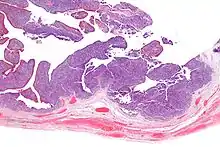

| Micrograph of transitional cell carcinoma of the ovary. H&E stain. |

Transitional cell carcinoma of the ovary (TCC of the ovary) is a rare type of ovarian cancer that has an appearance similar to urothelial carcinoma (also known as transitional cell carcinoma).[1]

TCC of the ovary is diagnosed by examination of the tissue by a pathologist. It has a characteristic appearance under the microscope and distinctive pattern of immunostaining.[2]

Very high mag.